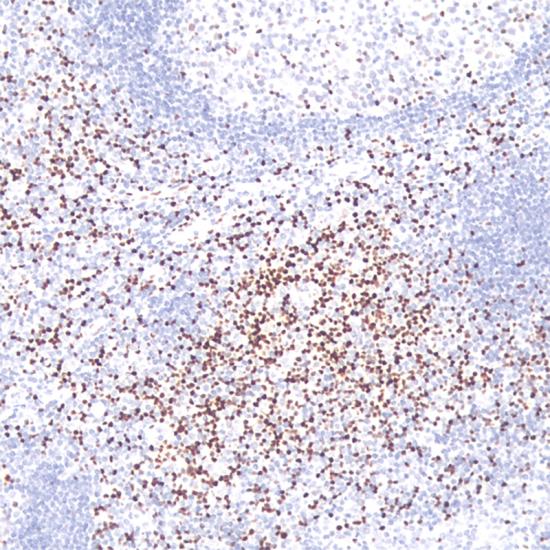

LEF-1

LEF-1抗體試劑(免疫組織化學) 閩廈械備20180130號

• 陽性部位:

細胞核

• 陽性對照:

扁桃體

• 適用組織:

石蠟

• 免疫顯色試劑:

iVision?

• 產(chǎn)品編號:

AR0590

• 種屬來源:

兔單抗

• 克隆號:

SD416

LEF1是一種核轉(zhuǎn)錄因子,調(diào)控細胞增殖及存活,正常表達于T細胞及前B細胞,而在成熟B細胞中不表達。LEF1在幾乎所有CLL/SLL中過度表達,不表達其它小B細胞淋巴瘤。